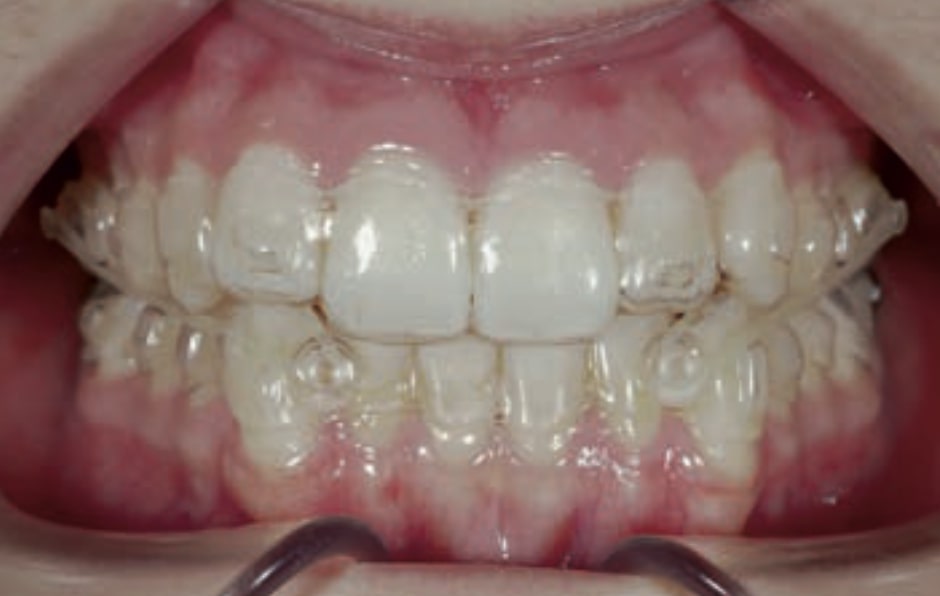

Chief complaint: The patient, a 19-year-old woman, was evaluated to undergo orthodontic treatment using the Angel Aligner Pro system. She presents with a skeletal Class III, mesofacial, with a dental Class III malocclusion and a 2 mm deviation of the lower midline to the left. Teeth 33 and 43 are out of the arch and cortical bone, with a crossbite issue on tooth 33. Fortunately, no functional issues affecting swallowing or breathing have been detected. The patient’s motivation for starting treatment was a general review of her dental and aesthetic health. The soft tissue analysis reveals mandibular protrusion that influences her facial profile. This diagnosis highlights the need for a comprehensive approach to address dental and skeletal misalignments, improving both the patient’s functionality and facial aesthetics.

Clinical examination and diagnosis

• Dental Class III, 2 mm deviation of the lower midline to the left. 33 and 43 out of the arch and the cortical bone.

• Crossbite of 33.